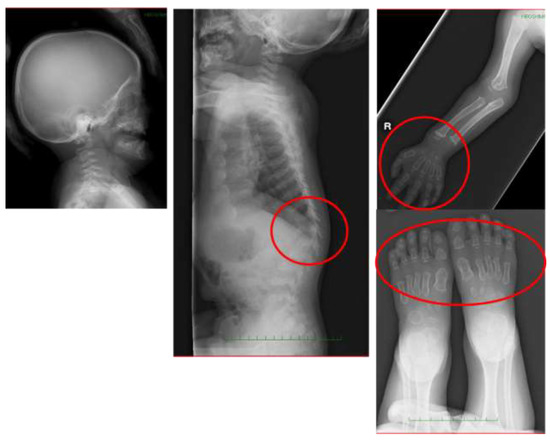

4. Diagnosis

6.4. Spinal Lesions